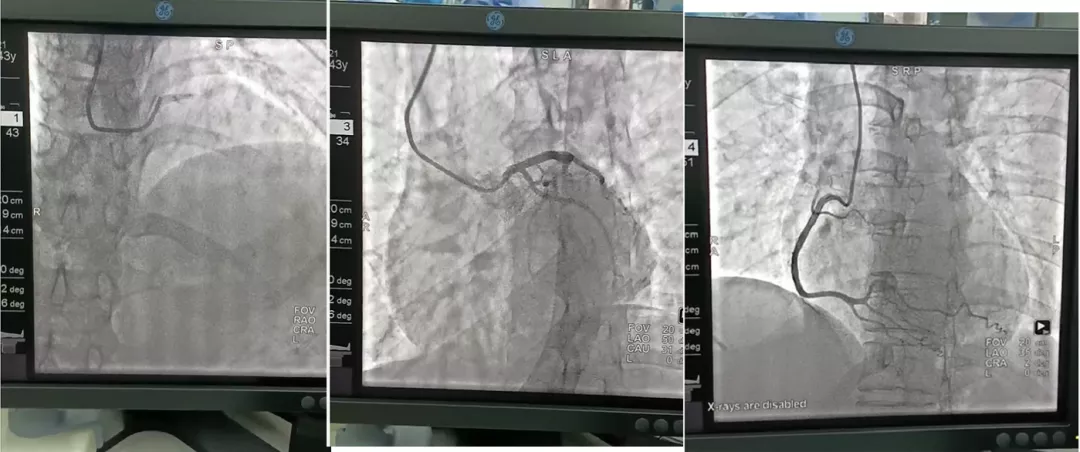

黄素贞主任介绍,冠状动脉造影术是诊断冠心病的“金标准”。通过冠状动脉造影,可以了解冠状动脉血管分布,发现冠状动脉是否有狭窄以及血管狭窄程度。根据冠状动脉造影结果,决定是否对狭窄血管进行支架置入术或者冠状动脉搭桥手术治疗。

新安医院冠状动脉造影术的开展,标志着医院在心脏介入手术的治疗技术取得了新的突破。经过了一年的精心准备,此次一举成功,不仅得到上级专家的高度认可,也为更好地服务于患者、保障生命健康打下坚实基础。